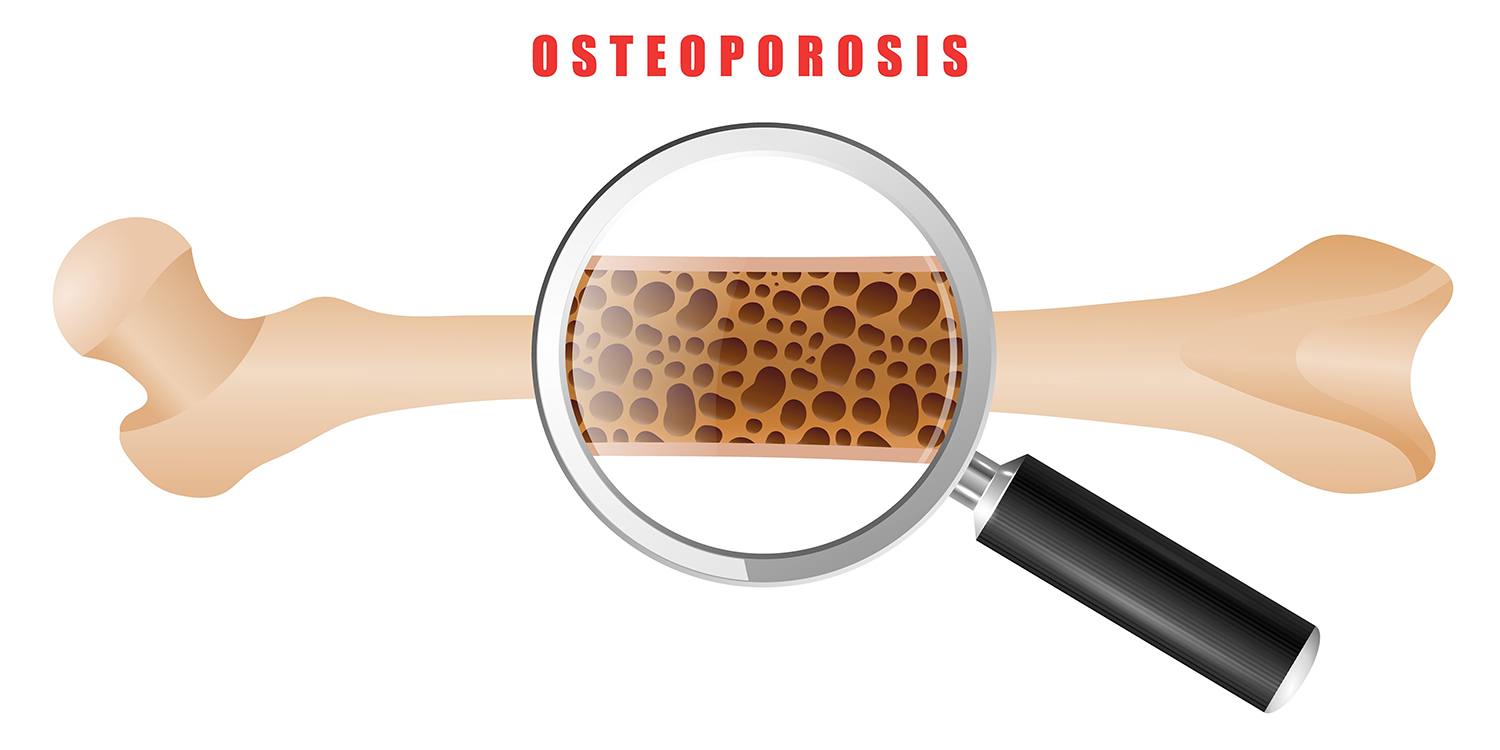

Bone Density Management and Osteoporosis Treatment

Bone health is a significant concern, especially in ageing patients. At Graphic Era Hospital, we provide comprehensive care for osteoporosis, helping patients manage and treat weakened bones to prevent fractures and maintain mobility.

What is osteoporosis, and how can it be prevented?

Osteoporosis weakens bones, making them prone to fractures. Prevention includes calcium, vitamin D, exercise, and lifestyle modifications.